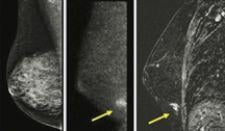

Magnetic resonance imaging (MRI) can be used for breast imaging as an alternative to mammography.

Mammography is the one breast cancer screening test proven to reduce mortality, yet on many occasions, it still does not ...